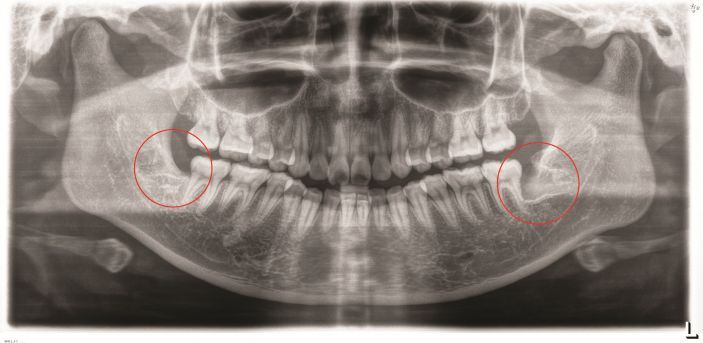

△智牙拔除前。

△智牙拔除後。

張主任講,微創拔智牙融合了多種先進的技術和理念,讓拔牙方式徹底告别盲目、暴力時代,具有這些優勢:1、個性化。術前通過CBCT明确患牙形态、埋伏深度及與下槽骨神經管、鄰牙的關系,分析骨阻力,設計、制定個性化的方案。2、創傷小。根據患牙特征,以減小創傷爲目的設計切口,采用超聲刀、切牙機等先進儀器設備,以小切口暴露牙冠,對患牙進行準确分割後經小切口逐一取出,告别傳統敲、鑿、劈、撬等一系列機械性操作,大幅度減少對正常組織的損傷。3、疼痛小、并發症少、恢複快。微創技術的應用,大幅減少智牙拔除的疼痛以及并發症,加快了術後的恢複。